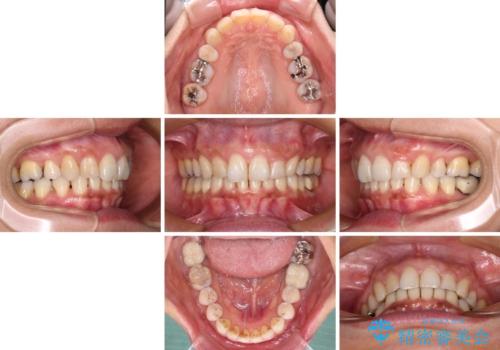

- 以前行った抜歯矯正が後戻りし、開いてしまったスペースが気になるとのことで来院された患者様です。

インビザラインを用いて開いてしまったスペースと前歯のデコボコを改善することとしました。

矯正治療後には気になっていた銀歯をセラミッククラウンやセラミックインレーにて治療することとしました。

上顎前歯を左右対称となるように歯列を整えたいとのことでしたが、すり減って形態が大きく異なっていたため、できる範囲での仕上がりとなりました。